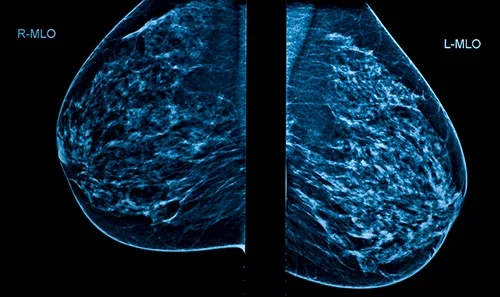

Mammografia to badanie przesiewowe w profilaktyce raka piersi | foto Medicover

Nowa Ruda. Systematyczna mammografia umożliwiają wykrycie zmian w piersiach na bardzo wczesnym etapie rozwoju, kiedy nie są one wyczuwalne podczas samokontroli piersi lub badań palpacyjnych. Wczesna diagnoza i natychmiastowe rozpoczęcie leczenia daje niemal 100% gwarancję powrotu do zdrowia.